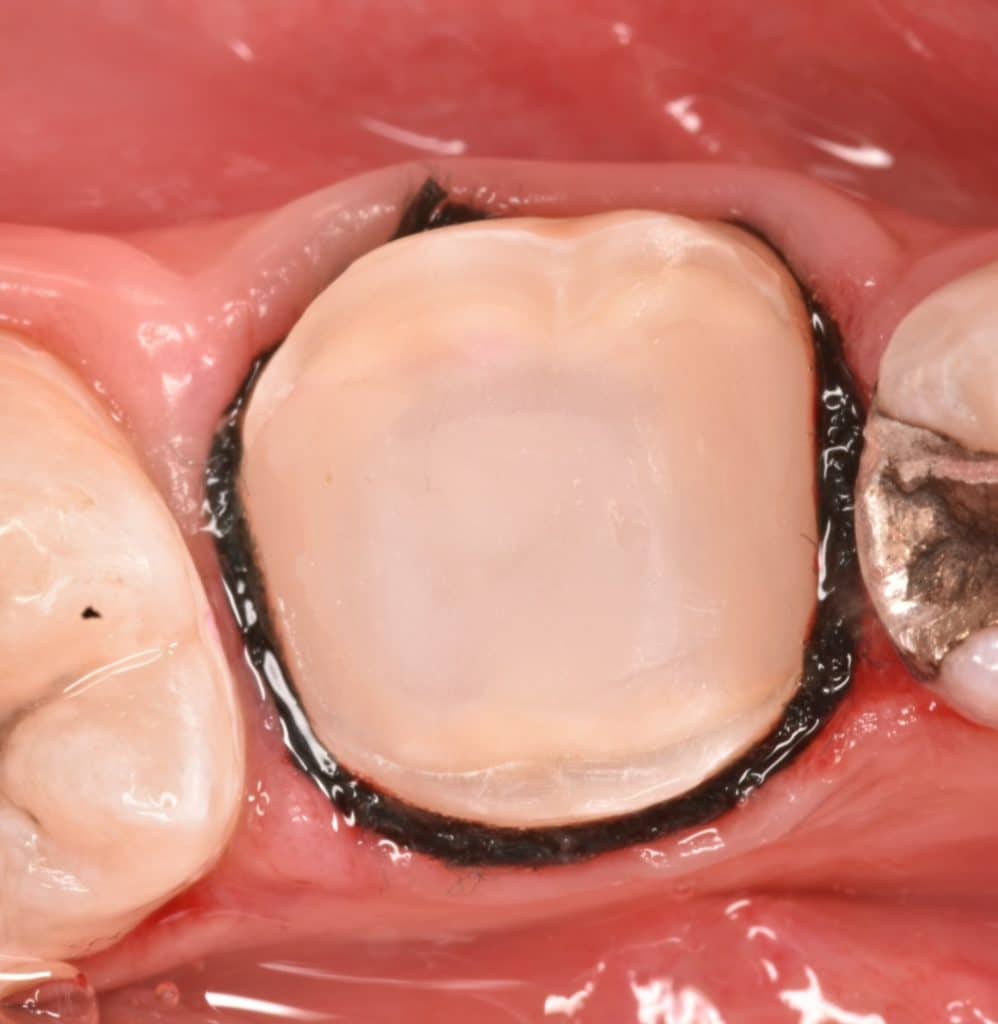

Initial situation , 10 years ago the patien did this endodontic treatment and amalgam filling

During amalgam removal

Old amalgam and screw removed